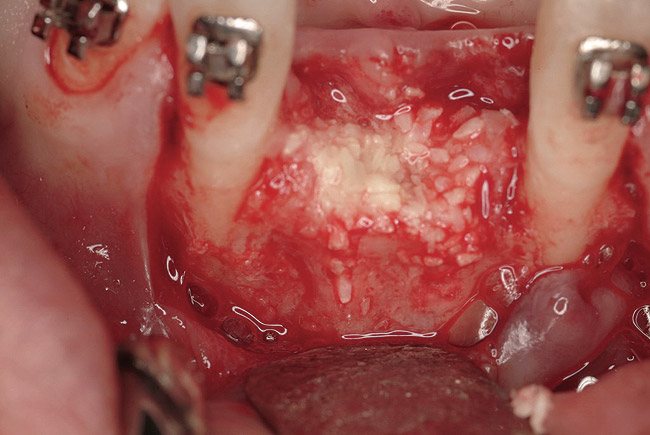

Figure 2  Tenacious soft tissue incorporates around titanium mesh, which is used for ridge augmentation and removed at time of implant placement.

Figure 2

Disadvantages to this technique include time necessary for mesh shaping, manipulation, and fixation. But perhaps the greatest shortcoming of titanium mesh is the necessity of its removal. This requires wide flap reflection and frequently sharp dissection (Figure 1). Often, a dense, soft-tissue layer is found over the mesh, referred to by Boyne10 as a “pseudo-periosteum.” This tenacious soft tissue is tightly bound to the mesh and underlying bone, requiring sharp dissection and elevation of the material. This adds significant operative time to the procedure. This type of soft tissue is shown in Figure 2; the mesh removed at the time of implant placement still has the tissue attached following sharp dissection and elevation. The wide flap reflection and time needed to remove the mesh increases morbidity associated with the second surgical procedure, primarily intended for implant placement. The evolution of this technique has led to the development of a rigid but resorbable mesh. The challenge for clinicians and researchers is to find a resorbable mesh capable of space maintenance comparable to titanium mesh, yet composed of a material that is biocompatible and does not compromise regenerative outcomes.